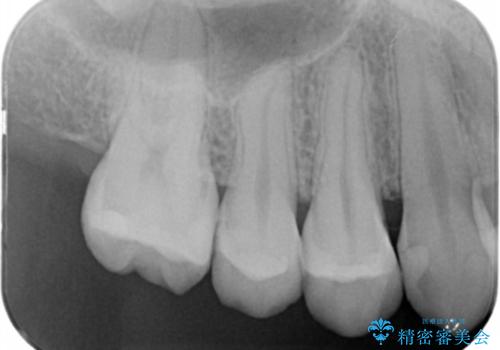

- 以前虫歯になり保険でプラスチックの詰め物をした部分の変色を主訴に、やり直しのご依頼を頂きました。

虫歯になった範囲が大きくなってくると削る範囲も比例して大きくなります。ある一定以上の大きさや範囲になった時の治療法に「インレー」というものがあり、保険の範囲では銀歯かプラスチック(適用条件有り)が、自費ではセラミックやゴールドといった素材を選ぶことができます。